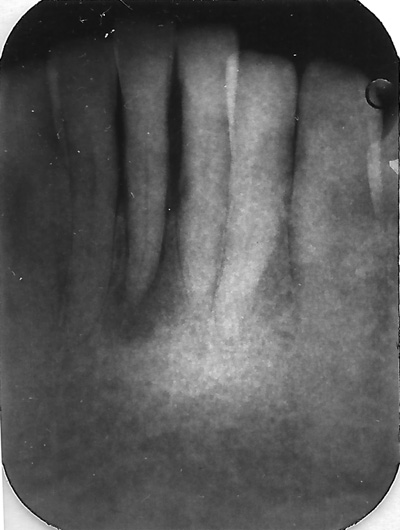

- Før behandlingen